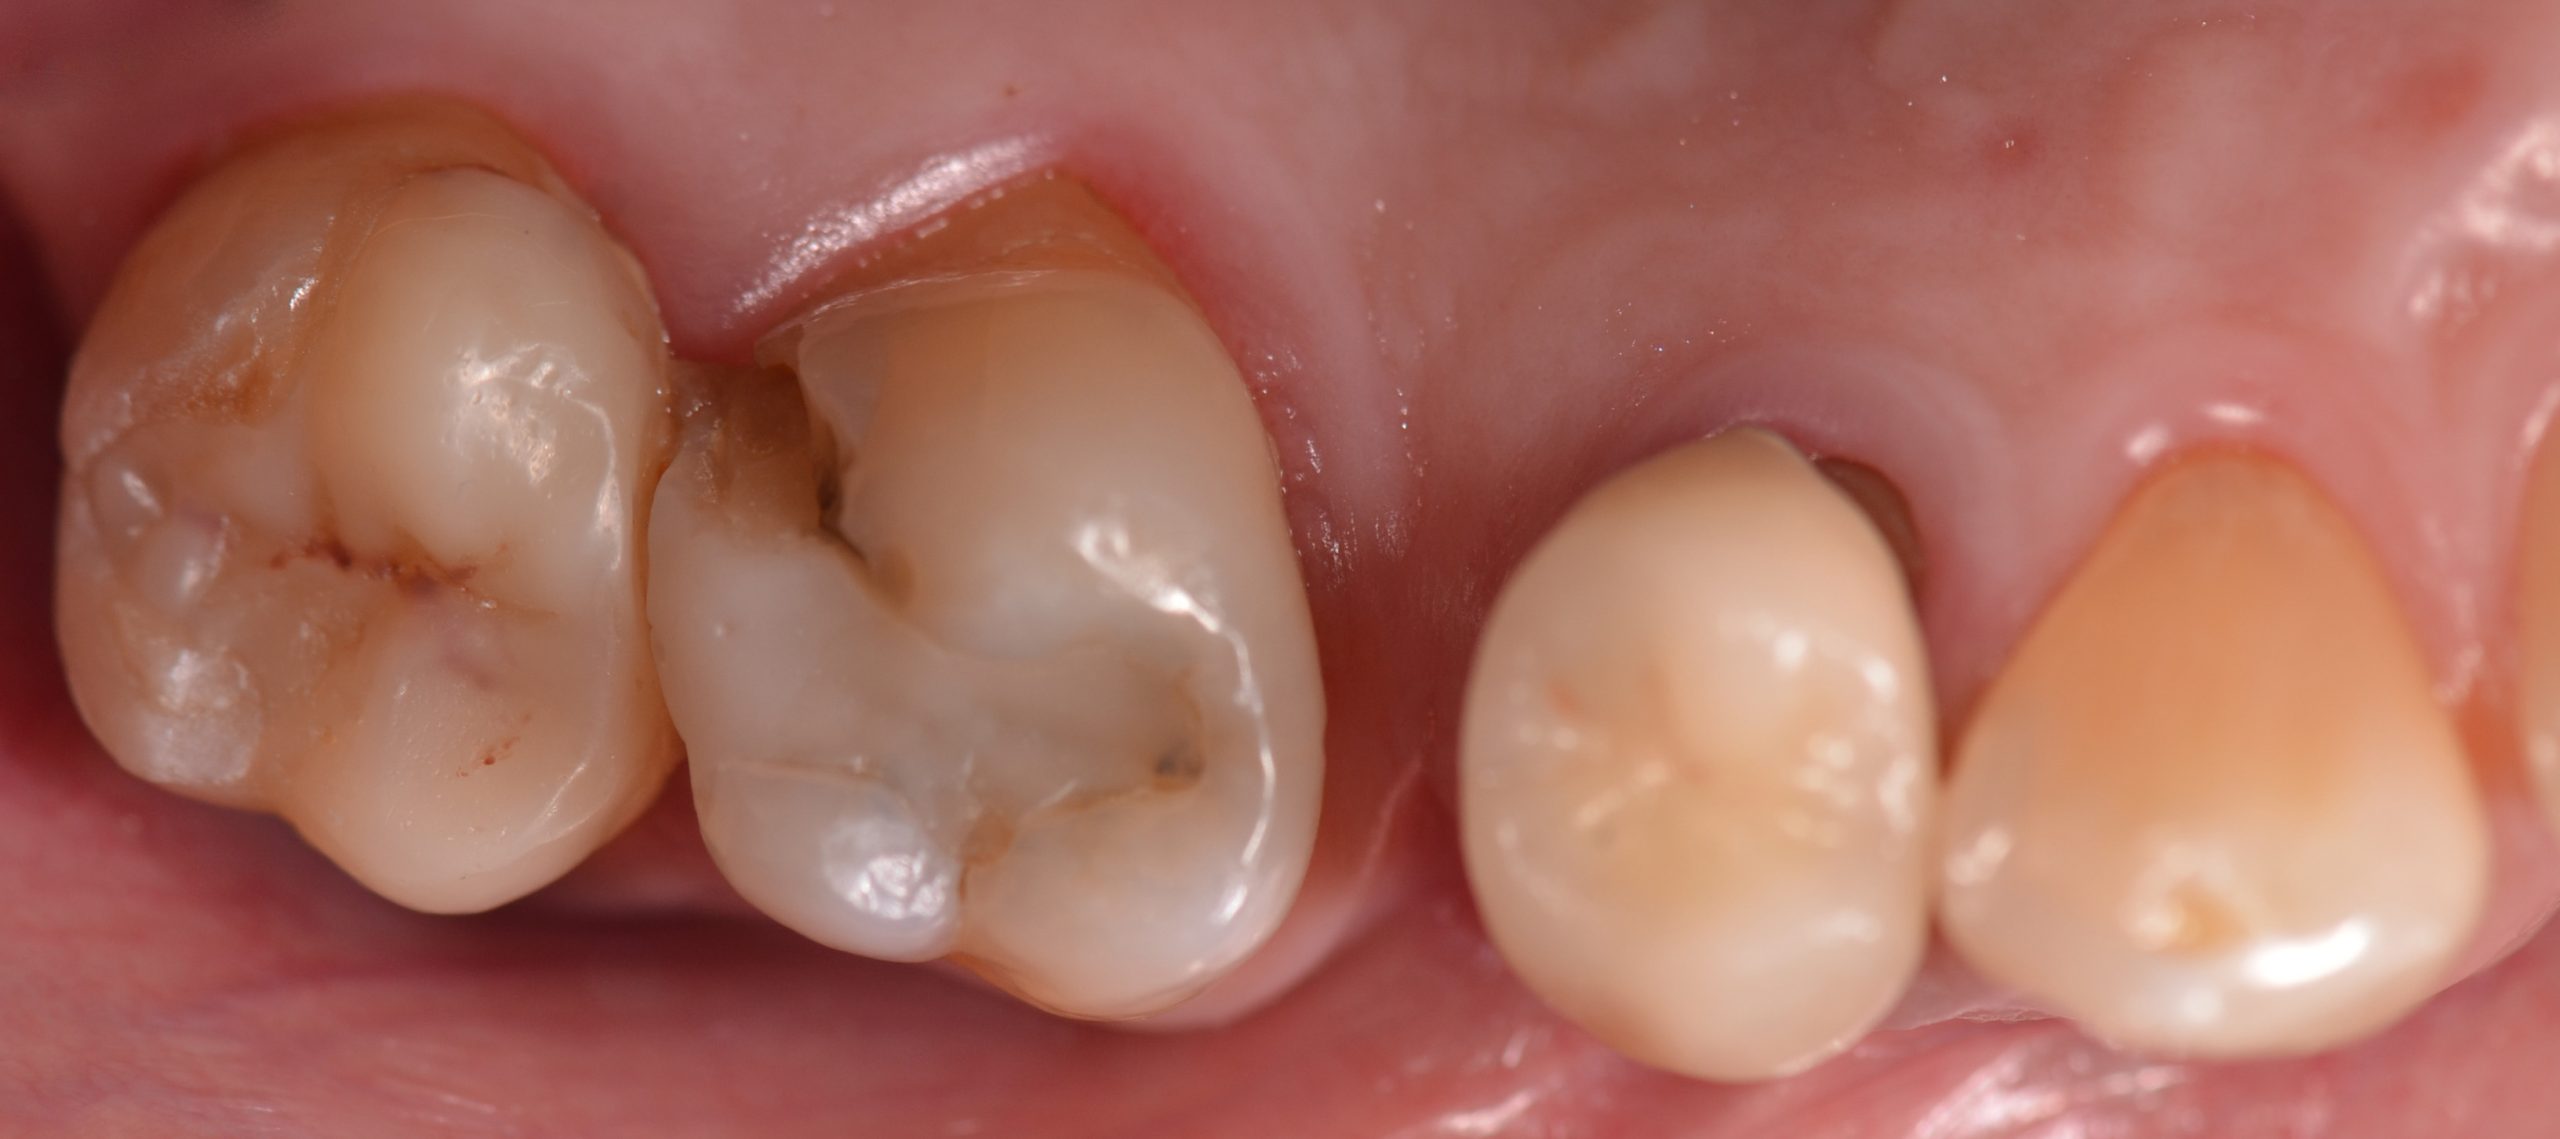

Una paziente di 44 anni si presenta alla nostra attenzione per la sostituzione di un vecchio restauro danneggiato. All’esame clinico si osserva la frattura della cuspide disto-palatina dell’elemento 1.6, associata a infiltrazione marginale di un restauro in composito incongruo. Le radiografie periapicali non evidenziano radiotrasparenze periapicali, ma mostrano possibili aree di demineralizzazione in zona marginale e all’interfaccia dente-restauro (1, 2, 3) (Figure 1-2).

Si esegue anestesia plessica con rinforzo intraligamentoso mediante articaina 1:100.000 sull’elemento 1.6. Successivamente si isola il campo con diga in gomma, utilizzando una clamp 27N sull’elemento 1.7 (Figura 3) con invaginazione del foglio a livello dei colletti.